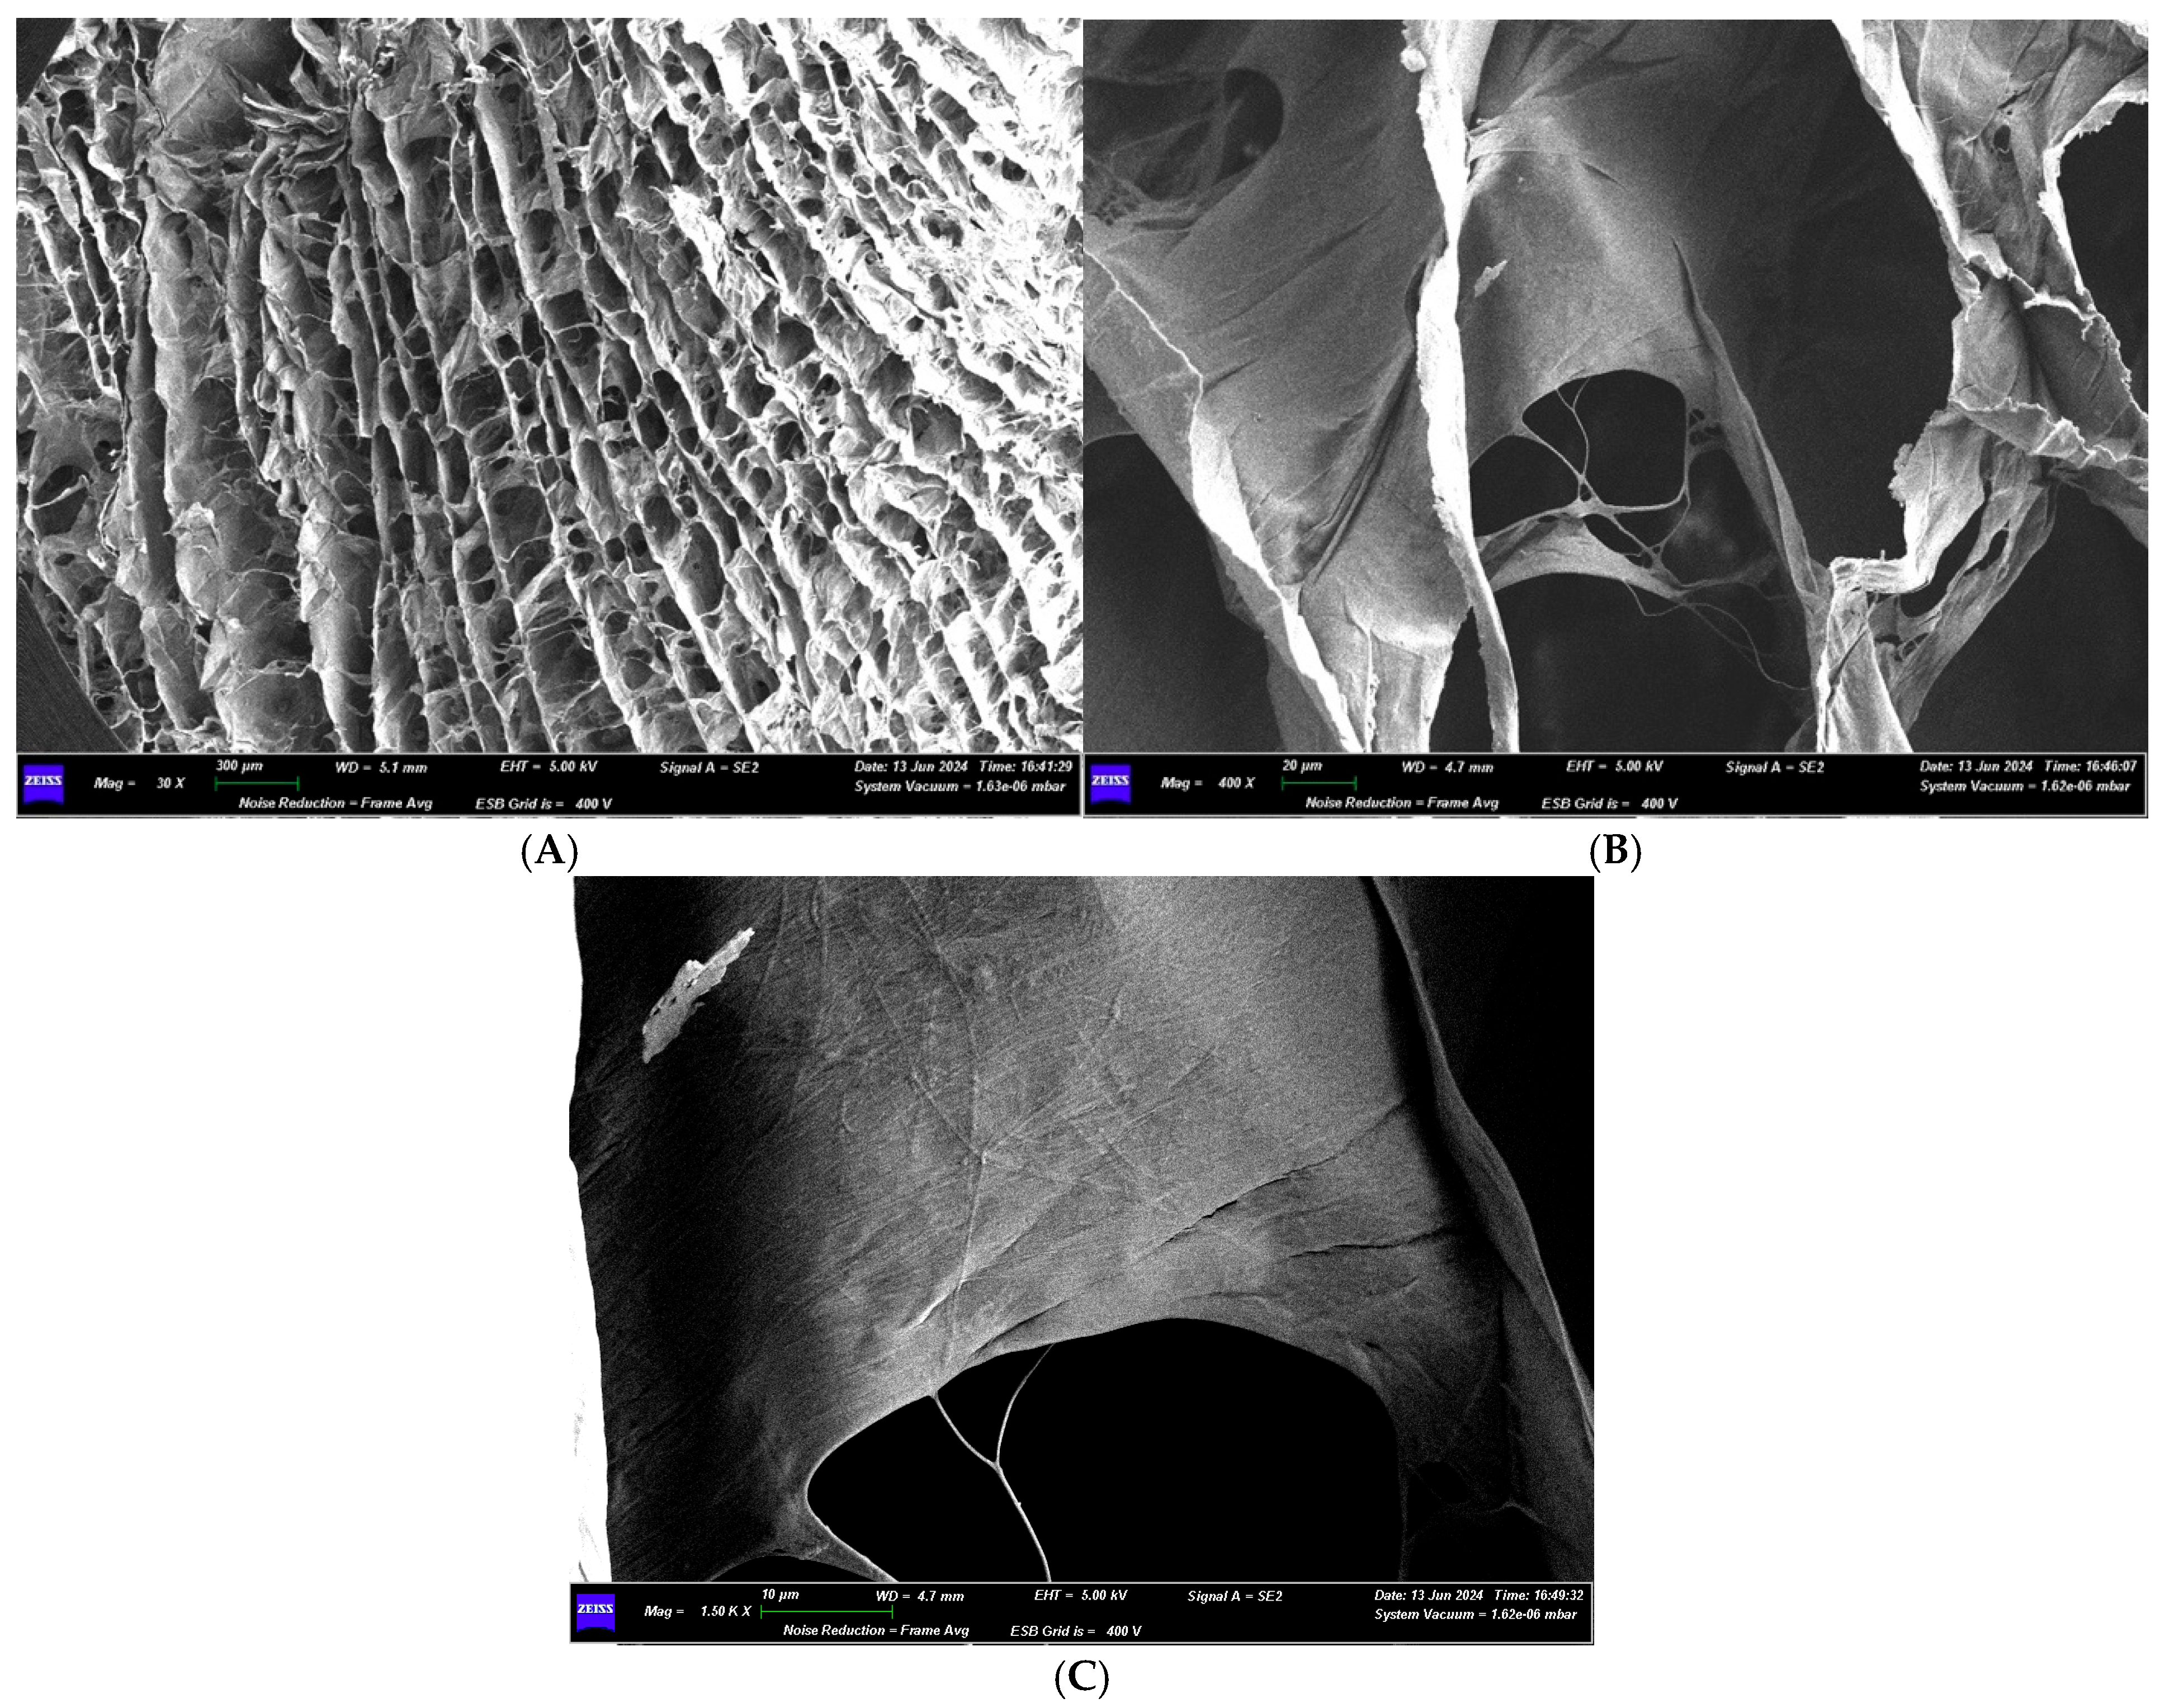

3.1.2. Optical Microscope and Scanning Electron Microscope Analysis

3.2.2. Optical Microscope and Scanning Electron Microscope Analysis

3.3.2. Optical Microscope and Scanning Electron Microscope Analysis

3.4.2. Optical Microscope and Scanning Electron Microscope Analysis

3.5.2. Optical Microscope and Scanning Electron Microscope Analysis